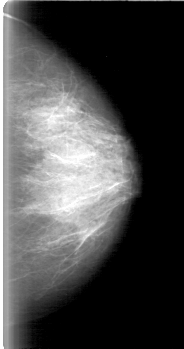

D_4018_1.LEFT_MLO

D_4018_1.LEFT_CC

LEFT_MLO LINES 5386 PIXELS_PER_LINE 2956 BITS_PER_PIXEL 12 RESOLUTION 43.5 NON_OVERLAY